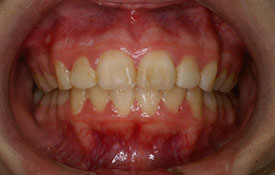

実際に山手矯正歯科クリニックにて、治療された方の例です。

インビザラインの治療例:CASE-1

| プロフィール | 42歳 女性 |

|---|---|

| 所見 | 他院で行われた矯正歯科治療後の後戻りに悩まれて来院されました。 アイライナーの装着は、1日平均20時間ほどでした。 |